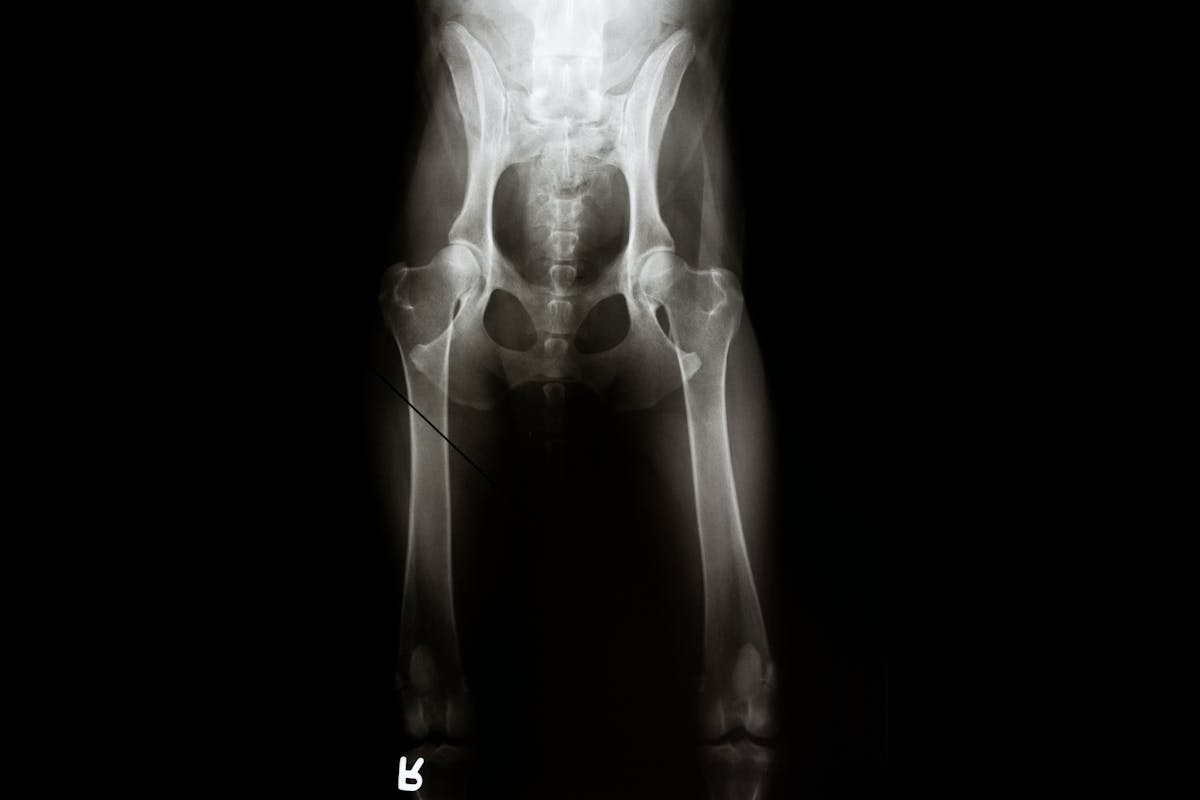

Hip dysplasia is a condition that develops as dogs age, resulting in laxity or instability of the joint. Over time, the abnormalities in the joint conformation can result in the breakdown of cartilage, and associated pain and lameness. Signs will vary depending on the severity of the dysplasia. The Orthopedic Foundation for Animals (OFA) is one organization that assesses and grades radiographs submitted for review. As part of their review, OFA sends submitted radiographs to three randomly selected board-certified veterinary radiologists for independent evaluation. Each radiologist reviews the x-rays, assessing nine different anatomic areas of the joint for deviations consistent with hip dysplasia. Breed, age, and sex are also considered in the assessment. A grade is assigned based on the phenotype, or appearance, of the hip conformation:

OFA numbers are only assigned to dogs that are 24 months of age or older at the time of radiograph. The OFA offers a preliminary evaluation for dogs under 24 months of age.

While not required, some form of chemical restraint, anesthesia or sedation, is recommended for muscle relaxation, optimum patient positioning and a truer representation of the hip status. Chemical restraint may minimize the need for repeat radiographs (less radiation exposure) while providing a less fearful experience for the dog.